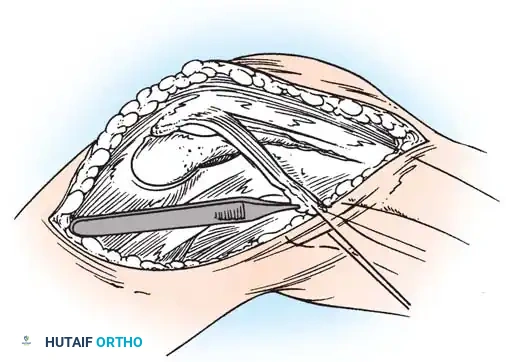

Fig. 45-17A: Hughston Reconstruction. A lateral one-fourth strip of the patellar tendon is meticulously developed, remaining attached at its proximal origin on the inferior pole of the patella.

Fig. 45-17B: The harvested strip is routed laterally and attached to the lateral tibial tubercle. Fixation is achieved either by direct suturing to the robust local periosteum or by passing the tendon strip through a dedicated bony tunnel for rigid osseous integration.

1. Tendon Harvest: Identify the lateral border of the patellar tendon. Longitudinally split the tendon to create a strip comprising the lateral one-fourth of its width. Detach this strip distally from the tibial tubercle, leaving its